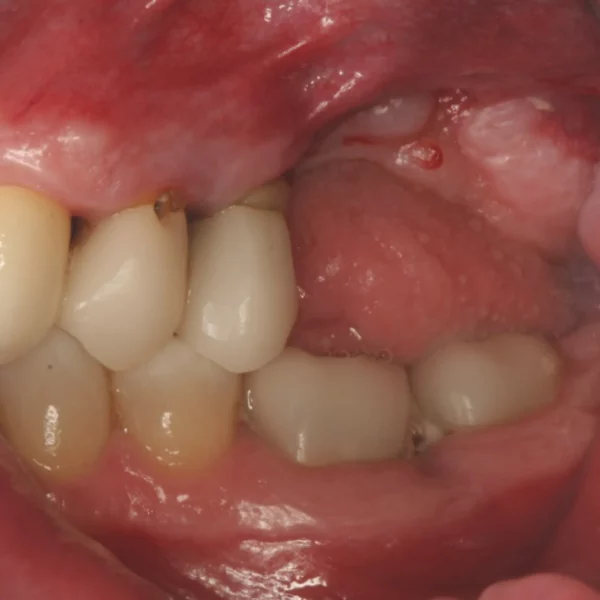

Der funktionelle und ästhetische Langzeiterfolg von Implantaten ist von einem ausreichenden Knochenlager bei Implantation abhängig. Du hast die Basiskenntnisse in der Implantologie erlernt und kommst aber immer wieder an Fälle, die dir zu komplex erscheinen? Dieser OP-Kurs vermittelt dir das Know-how zu augmentativen Techniken, um defektabhängig therapieren zu können. Praktisch können erlernte Techniken am Humanpräparat umgesetzt werden.

• Weichgewebsmanagement